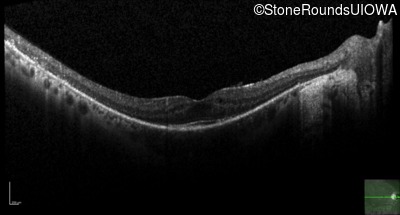

Optical Coherence Tomography - Right - 20/20

Exemplar / OCT Stack